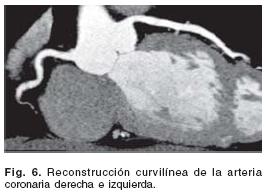

Se recomienda no borrar los datos crudos (raw data), hasta que el estudio no haya sido interpretado y no se requiera información adicional. Para una mejor visualización del árbol coronario en su totalidad, las imágenes son enviadas a una estación de diagnóstico donde se pueden revisar en múltiples formatos de presentación:5,16 reconstrucción multiplanar y curviplanar (MPR/ CPR) (Fig. 6), máxima intensidad de proyección (MIP) (Fig. 7) o reconstrucción volumétrica (VR, volume–rendering) (Fig. 8). Generalmente se emplean dos formatos de reconstrucción (MPR y MIP) para la interpretación multiplanar y representación 3D: oblicua anterior derecha para la CD, oblicua anterior izquierda para la CI, y oblicua lateral izquierda para las arterias DA y Cx.16 Desde estas proyecciones básicas se puede angular ligeramente el plano con dirección craneal o caudal para evaluar las diferentes ramas y sus porciones distales.16 La interpretación se hace siguiendo la nomenclatura modificada de la AHA,45 donde el segmento 16 corresponde al ramo intermedio. Los hallazgos positivos siempre se deben de corroborar en por lo menos 2 planos ortogonales. La representación de volumen (4D) es especialmente útil para evaluar el trayecto de los puentes coronarios, así como las anomalías y fístulas coronarias.